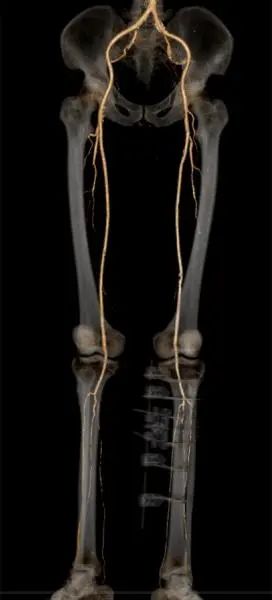

术前CTA影像:胫前胫后动脉闭塞

术后CTA影像:胫前胫后动脉通畅开放

通过近2个月的治疗,倪大爷的大部分右足溃疡得到了修复,感染也彻底控制住了。更可喜的是,术后再次复查下肢动脉血管造影,原本闭塞的动脉竟然变通畅了,包括未进行手术的右下肢血管闭塞也得到了改善:正是因为血管的再通,恢复血液循环后的下肢溃疡才最终能完成修复。